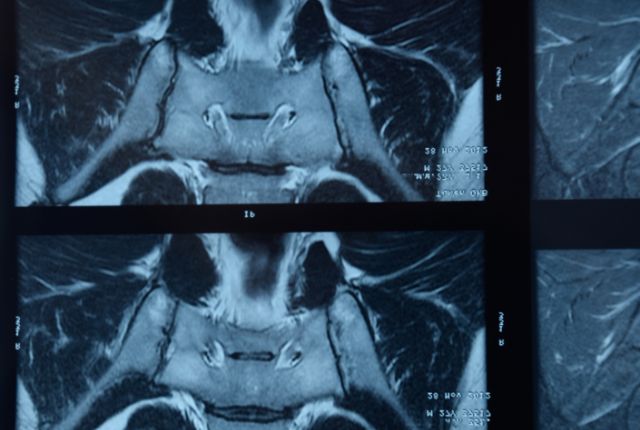

L’interrogatoire médical aide à poser le diagnostic. Le médecin interroge le patient sur le type de douleurs, leur localisation… En plus de l’examen clinique, des radiographies des articulations et des échographies des enthèses sont prescrites. Des examens complémentaires tels qu’un scanner ou une IRM permettent de connaître le degré d’atteinte des articulations.